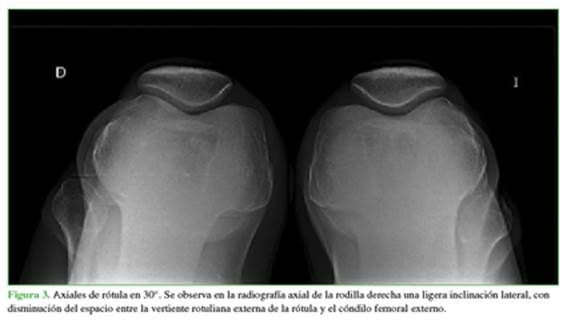

Se solicitaron radiografías en el frente y perfil, que fueron negativas, y estudio axial de ambas rótulas en 20° y 45° (Figura 3).